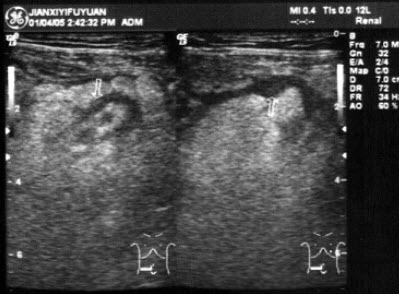

男,63岁,因左侧腰部疼痛不适伴无痛血尿1月余就诊,B超显示左肾集合系统分离3.9cm,如图所示,最可能的诊断为()

A.左输尿管结石

B.左输尿管癌

C.左输尿管炎性狭窄

D.左输尿管畸形

E.左输尿管血块

22、单项选择题 子宫先天性发育异常常伴有哪个器官异常()